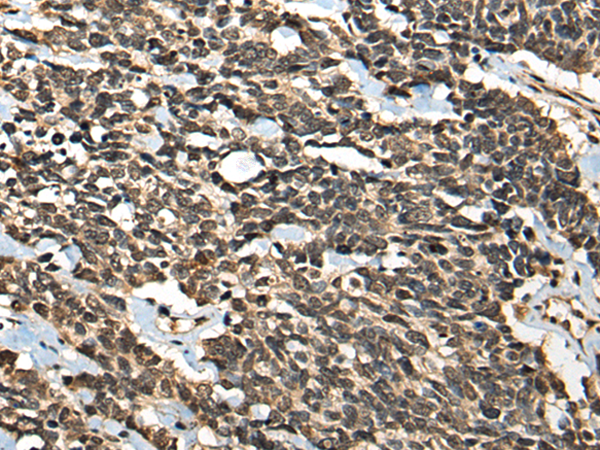

分类: 科研抗体货号: P02516别名: VPS20应用: WB,IHC反应种属: Human, Mouse